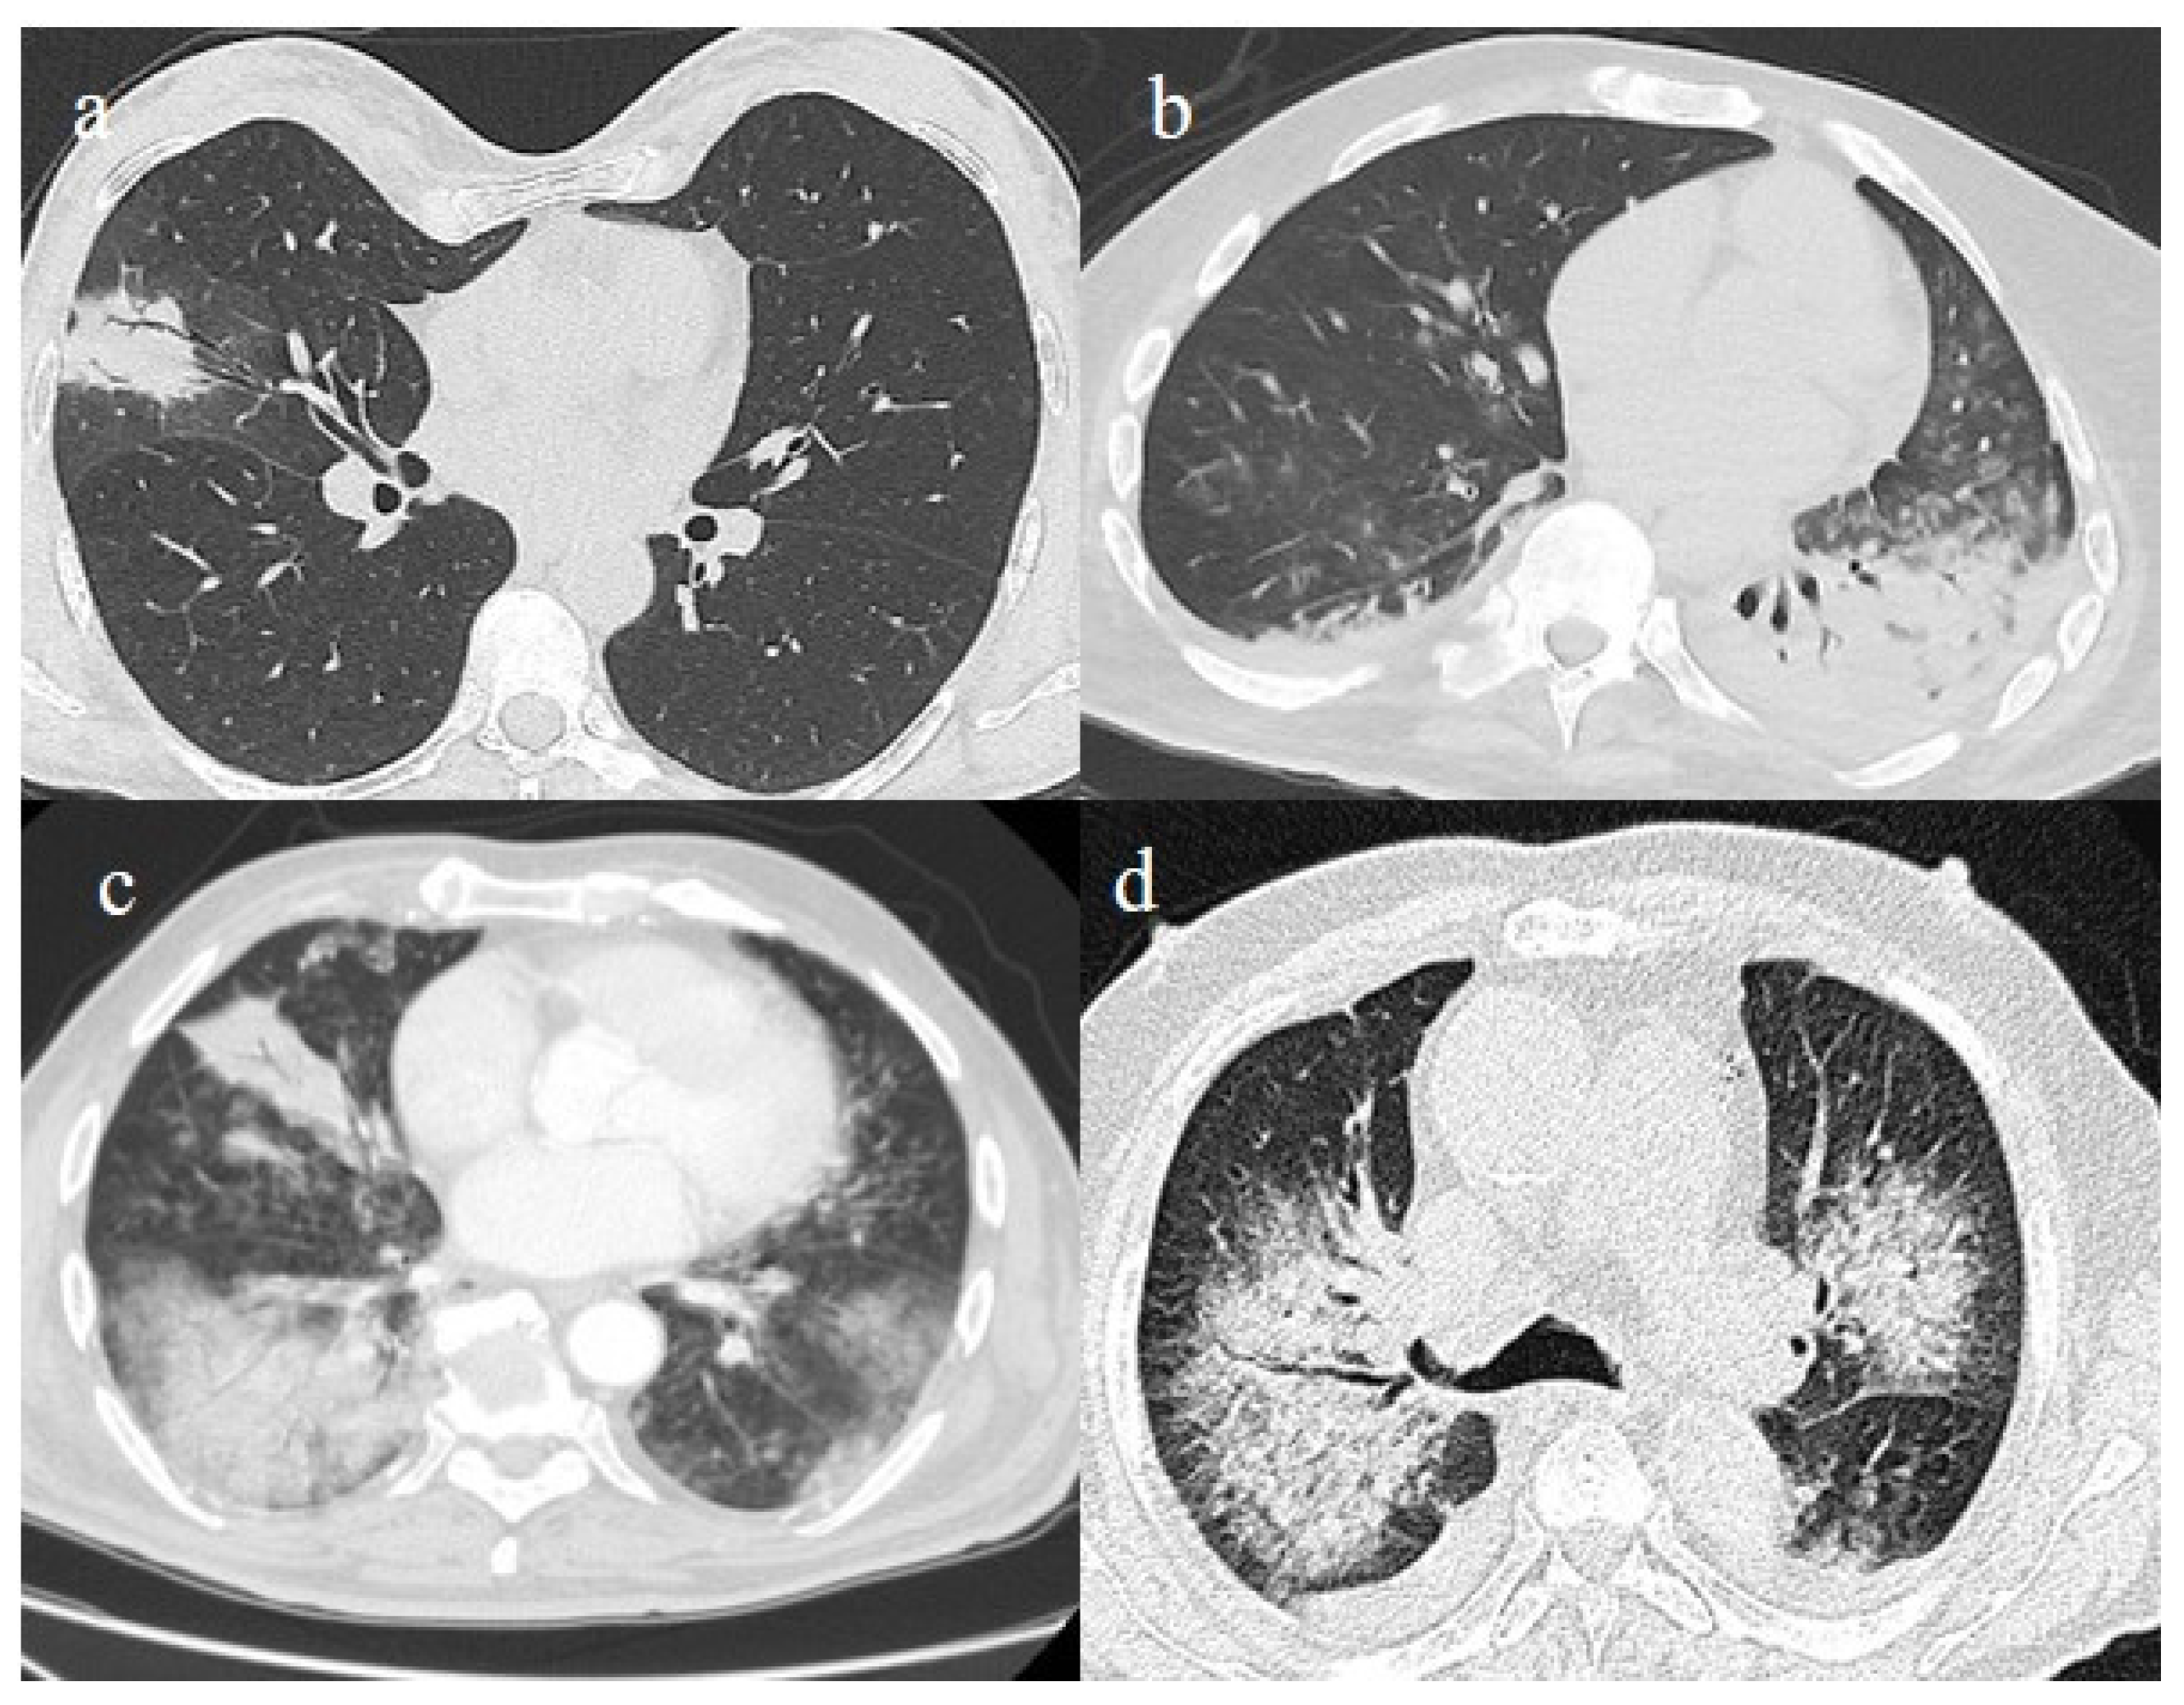

3.3.1. Acute Respiratory Distress Syndrome

3.3.2. Pneumomediastinum and Pneumothorax

3.3.3. Pulmonary Fibrosis

3.3.4. Pulmonary Thromboembolism

| Typical Appearance | GGOs with a crazy-paving pattern and consolidations in a peripheral and posterior or central-peripheral distribution; multilobar involvement; vascular enlargement, the halo and reversed halo sign; subpleural and parenchymal bands; and architectural distortion. They were predominant since the Delta wave. |

| Atypical Appearance | Lobar consolidation, lung nodules or masses, miliary patterns, tree-in-bud patterns, cavitation, pleural effusion, central distribution, and lymphadenopathy. Atypical appearances were predominant during the Omicron waves. |